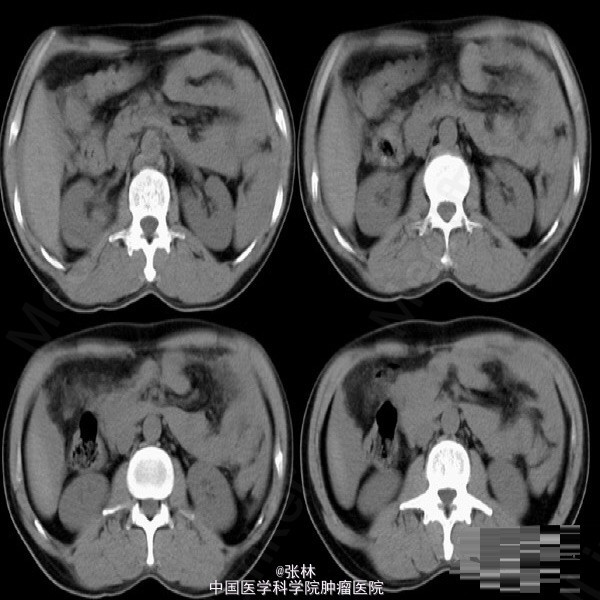

【病史临床】患者,男性,44岁,上腹外伤,疼痛伴呕吐2小时之主诉来诊。CT表现:肝脏周围积液征象,脾脏形态不规则,脾周可见略高密度影。 结果:手术记录如下:(剖腹探查)取上腹正中切口,探查见腹盆腔有较多的积血和血凝块,脾脏表面凹凸不平,肝、脾周有积血。收除腹盆腔积血约1000ML。仔细探查于脾上极脏面可见一深约2cm,长约4cm裂口,时有出血。 最后诊断:外伤性脾破裂。